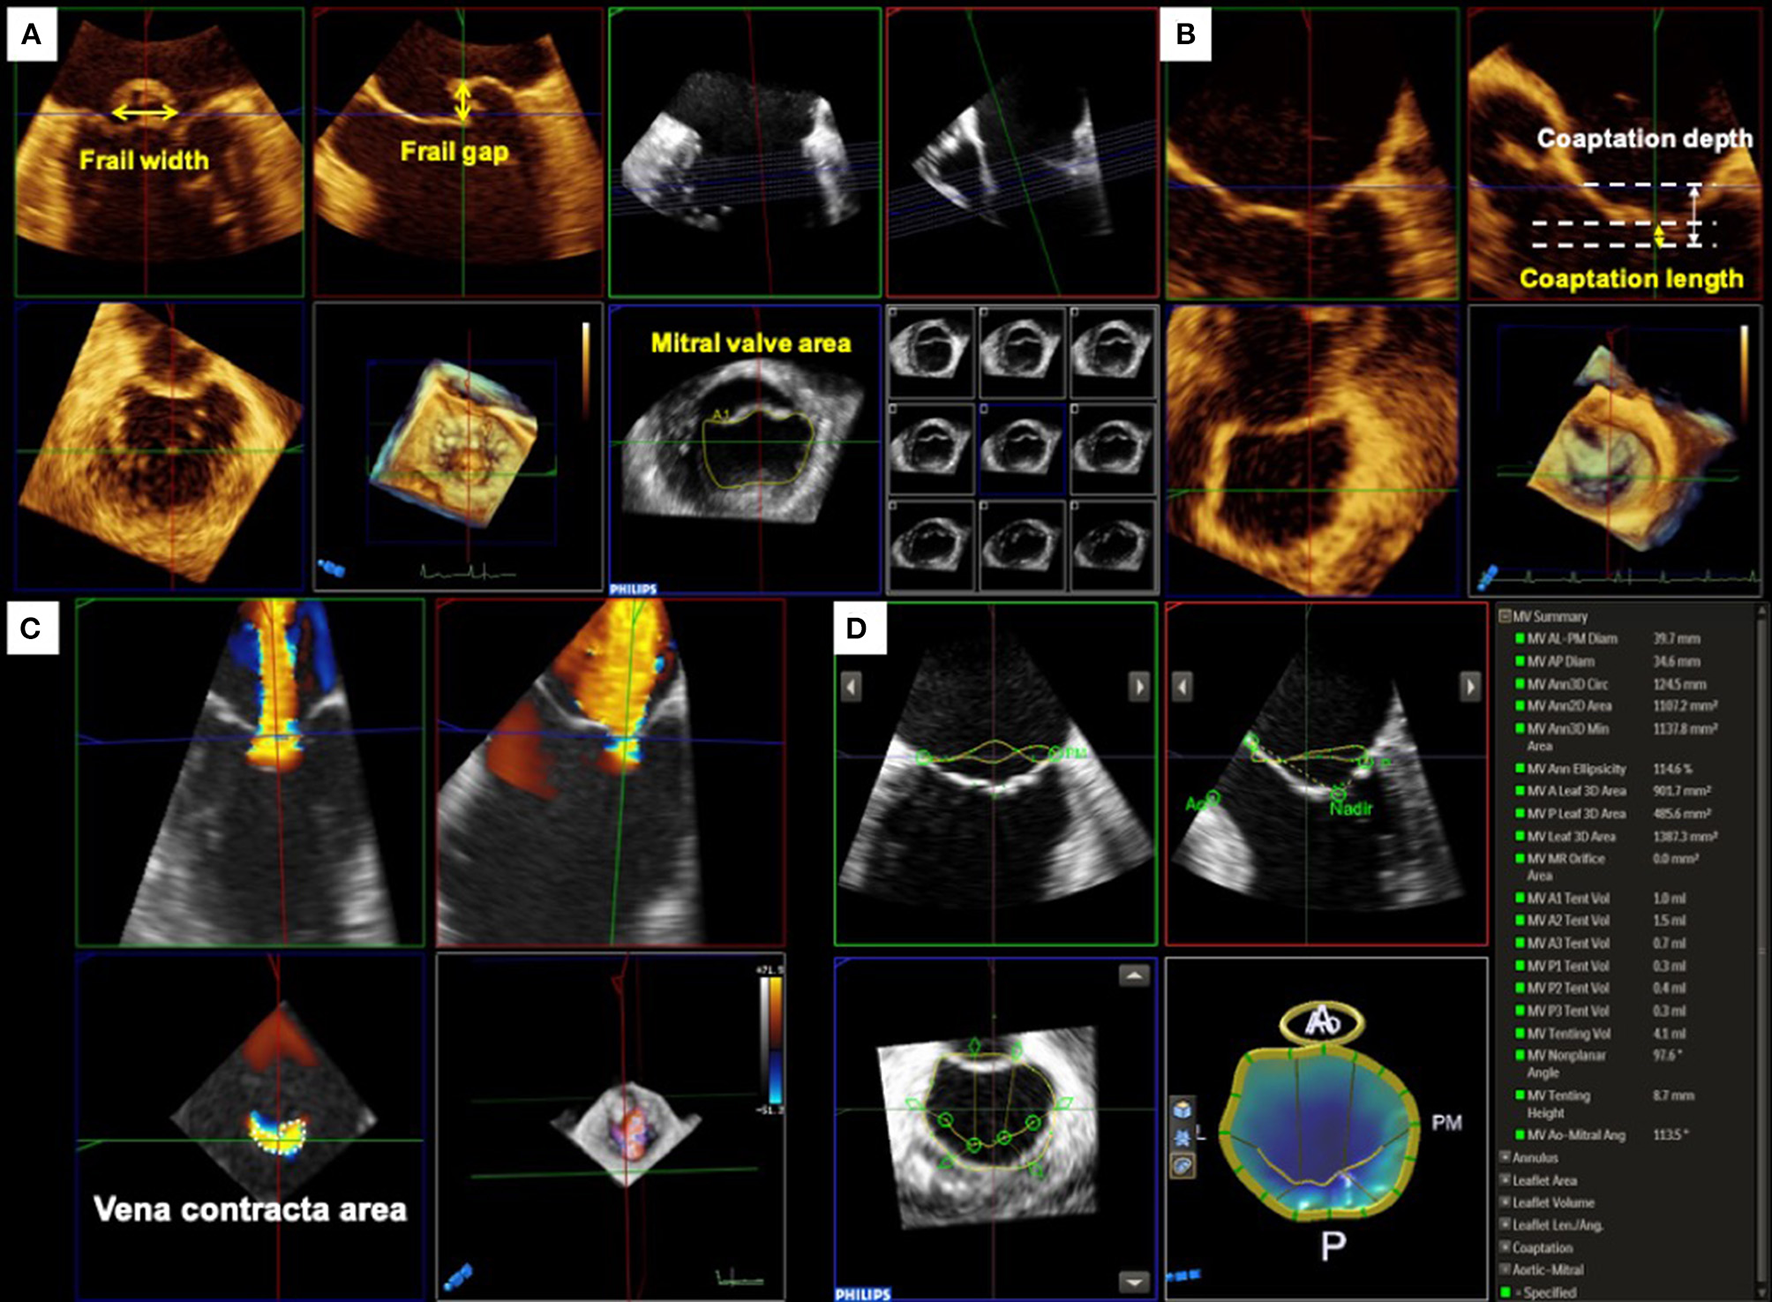

Primary MR is characterized by degenerative alterations of the MV leaflet such as prolapse and/or frailty. Three-dimensional TEE allows to visualize the comprehensive anatomy of the MV and is helpful for easy understanding of the diseased lesion resulting from the degeneration. Moreover, a quantitative evaluation of MV anatomy must be performed to identify patients who will benefit from the procedure. In the EVEREST trials, several anatomical criteria for primary MR were used as follows; a frail gap <10 mm and a frail width <15 mm (10). In addition, several exclusion criteria, such as severe leaflet calcification in the grasping zone, leaflet perforation, significant cleft, and MV opening area <4 cm2, were defined. However, these measurements are sometimes difficult to assess using only conventional 2D images. Using 3D TEE with multiplanar reconstruction, a more accurate measurement of these dimensions can be obtained (Figure 1A).

Figure 1

Pre-procedural assessment and quantification of mitral valve geometry. (A) Primary mitral regurgitation. For treating primary MR with MitraClip, the frail gap and width of the lesion and mitral valve opening area are used for assessing the procedural durability. (B) Secondary mitral regurgitation. Whereas, the coaptation depth and length should be evaluated for secondary MR. (C) Quantification of mitral regurgitation by three-dimensional (3D) color Doppler. Three-dimensional vena contracta area allows to evaluate regurgitant orifice area directly and may improve the assessment of regurgitant severity. (D) MV geometrical assessment using Mitral Valve NavigatorA.I.. Semi-automated software dedicated to MV quantification provides useful information on the MV geometry from 3D TEE images.

Color Doppler 3D echocardiographic image is also informative for understanding the characteristics of MR. In many cases of primary MR, the eccentric direction of the regurgitant jet is commonly observed. Thus, it may be difficult to plan an optimal clip position. Color Doppler 3D TEE images depict the accurate location of the regurgitant orifice and the jet direction, which may help in planning the ideal positioning of the MitraClip.

In contrast, secondary MR is defined as MR due to LV and/or LA dysfunction without abnormalities in the MV leaflet and chordae tendineae (11). Although severe secondary MR is associated with adverse prognosis (12–14), the optimal treatment remains controversial. A recently published COAPT trial showed an incremental benefit of MitraClip implantation in addition to guideline-directed medical therapy in patients with symptomatic severe secondary MR at high surgical risk. In contrast, the Multicenter Study of Percutaneous Mitral Valve Repair MitraClip Device in Patients with Severe Secondary Mitral Regurgitation (MITRA-FR) trial showed no significant improvement in outcomes in patients treated with MitraClip. (15) The discrepancy in the results of these two randomized controlled trials may be due to the baseline characteristics of patients. Thus, the indications for TMVr therapy should be carefully evaluated (Figure 1B).

Quantitative assessment of MR severity is crucial for determining the indications for TMVr. However, quantitative assessment of secondary MR using 2D echocardiography has several limitations. In many cases with secondary MR, the flow convergence zone is not hemispherical and the regurgitant orifice has an oval or a crescent shape (16). Thus, the calculation derived by the proximal isovelocity surface area (PISA) method using 2D echocardiography can easily underestimate the MR severity (17, 18). Color Doppler 3D TEE and the multiplanar reconstruction provide a direct measurement of the regurgitant orifice area (3D VCA) which may improve the accuracy of MR grading (Figure 1C).

The MV geometry is also an important factor for considering the durability of TMVr. The COAPT trial used two anatomical inclusion criteria for secondary MR; coaptation length ≥2 mm and coaptation depth <11 mm. Several semi-automated echocardiographic software dedicated to 3D MV geometry have been introduced and applied for pre-procedural evaluation in clinical practice. MV area, perimeter, and leaflet area derived from 3D images can be measured using the software and may provide further incremental information about the degree of tenting and/or leaflet remodeling (19, 20) (Figure 1D).